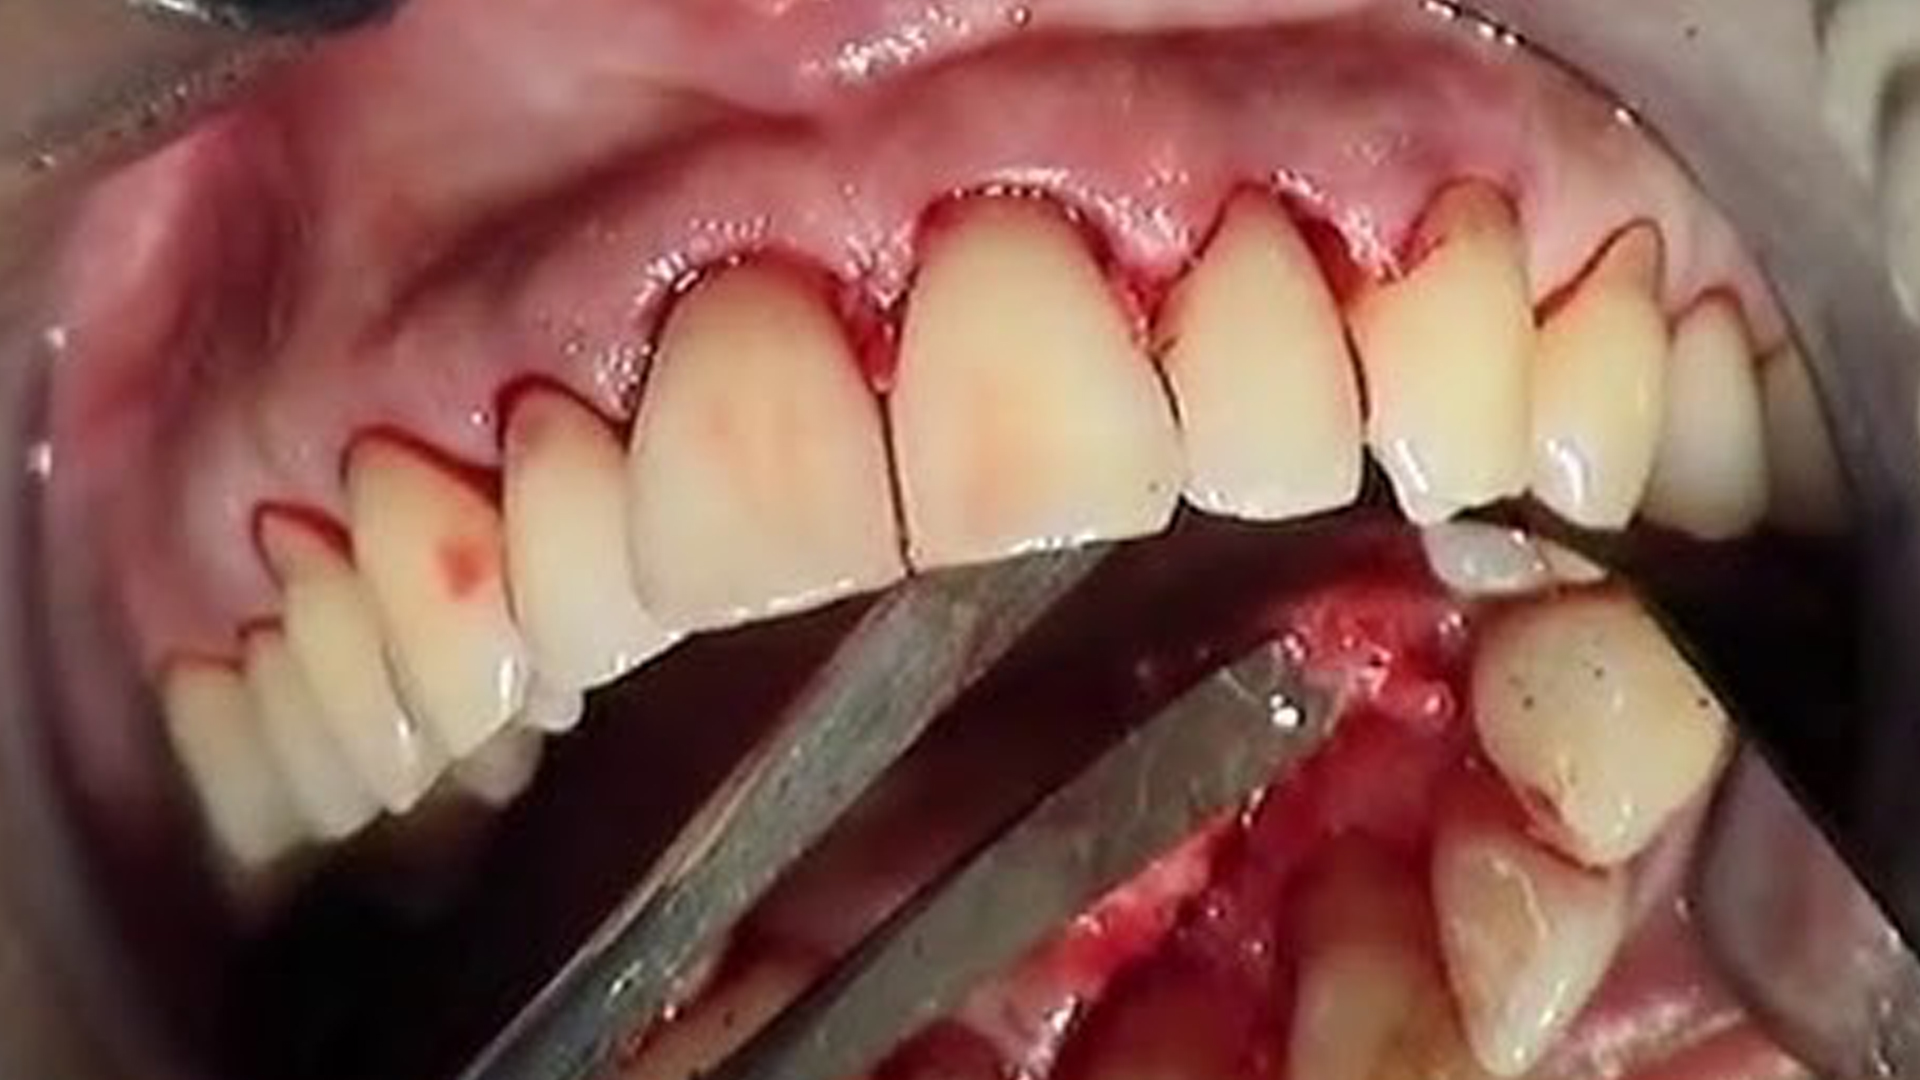

Cette infection est principalement due à une mauvaise hygiène dentaire, qui permet aux bactéries de s’accumuler entre les dents et les gencives et finissent par former une plaque dentaire, collant aux dents et constitué de protéines salivaires, de déchets alimentaires (sucres et acides) et de bactéries. Lorsqu’il se calcifie, cet enduit blanc et opaque constitue le tartre qui peut, avec le temps, entraîner une infection chronique. Outre cette plaque dentaire recouvrant les dents du patient, les premiers signes avant-coureurs de la maladie parodontale sont la présence de poches parodontales, ou d’inflammation des gencives, et le saignement gingival. Outre un mauvais brossage des dents, plusieurs facteurs aggravants peuvent expliquer l’apparition de la parodontopathie.

Après la gingivite, l’infection bactérienne des tissus gingivaux affecte les tissus de soutien des dents, contribuant à une aggravation de la maladie parodontale. Lorsque la gencive et l’os alvéolaire se rétractent, la parodontite devient chronique, la dent perd son soutien et commence à bouger. En l’absence de traitement adéquat, l’os poursuit sa rétractation et la dent infectée n’est plus tenue par le parodonte, finissant par tomber. Parvenue à ce stade terminal, la parodontite ne peut plus être soignée. Il est alors nécessaire d’extraire la dent infectée, et de procéder à son remplacement par une prothèse dentaire soutenue par un implant, vissé dans l’os maxillaire. En effet, en l’absence de dent “active”, l’os n’est plus sollicité et poursuit sa rétractation, tandis que l’infection continue son travail de sape sur le parodonte des dents voisines.

Reconnaître les symptômes des différents stades

Ne sous-estimez jamais un mal de dents : il peut être le signe d’une parodontite, qui conduit systématiquement à une aggravation chronique de la maladie. Au stade précoces, les principaux signes avant-coureurs d’une parodontite sont :

• Des gencives qui saignent

Lorsqu’un patient note la présence d’un ou plusieurs de ces symptômes, il doit immédiatement consulter un dentiste qui pourra déceler une maladie parodontale et son niveau d’évolution. Au stade terminal ou de nécrose, d’autres signes symptomatiques peuvent être rapidement décelés :

• Douleur intense au niveau des racines de la dent

• Abcès parodontaux et apparition de pus à la base des gencives

• Dents qui bougent

• Mauvaise haleine

• Perte de dents